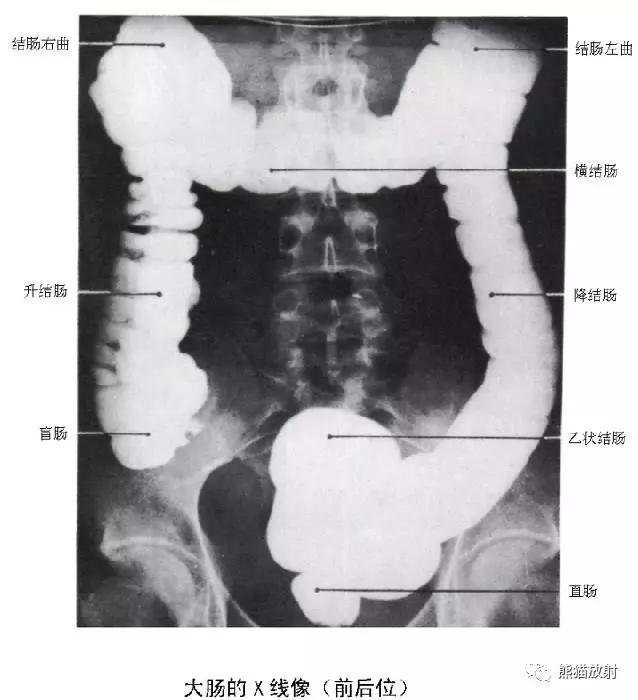

10 Colon 结肠

1 Splenic flexure of the colon 结肠脾曲,2 Hepatic flexure of the colon 结肠肝曲,3 Ascending colon 升结肠,4 Transverse colon 横结肠,5 Descending colon 降结肠,6 Haustra 结肠袋,7 Ileocecal valve 回盲瓣,8 Cecum 盲肠,9 Sigmoid colon 乙状结肠,10 Appendix 阑尾,11 Rectum 直肠

11 Rectum 直肠

1 Rectosigmoid junction 直肠乙状结肠连接部,2 Sacrum 骶骨,3 Retrorectal space 直肠后间隙,4 Transverse rectal fold 直肠横襞,5 Femoral head 股骨头,6 Rectal ampulla 直肠壶腹部,7 Coccyx 尾骨,8 Anorectal junction 肛门直肠交界处